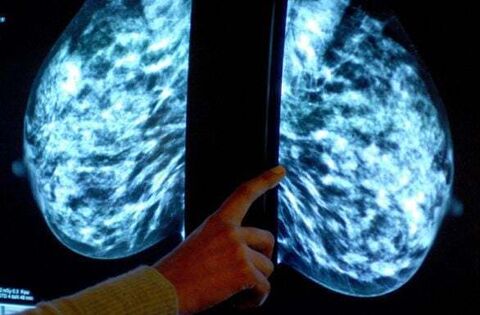

It was claimed the HSE allegedly failed to provide appropriate care for Ms Halligan, and that there had been an alleged failure to carry out an appropriate triple assessment of a mass on her right breast, including a biopsy when she was assessed at the Breast Clinic at University Hospital Waterford on June 4th, 2014.

There was, it was further claimed, a delay in the treatment of Ms Halligan’s breast cancer, and there was an alleged failure to refer Ms Halligan for a breast MRI scan after an irregular lump was recorded on June 4th, 2014, and noted by a consultant surgeon as suspicious for cancer and probably malignant.